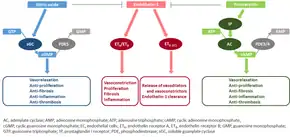

The molecular mechanism of pulmonary arterial hypertension (PAH) is not known yet, but it is believed that the endothelial dysfunction results in a decrease in the synthesis of endothelium-derived vasodilators such as nitric oxide and prostacyclin.[39] Moreover, there is a stimulation of the synthesis of vasoconstrictors such as thromboxane and vascular endothelial growth factor (VEGF). These result in a severe vasoconstriction and vascular smooth muscle and adventitial hypertrophy characteristic of patients with PAH.[39]

Nitric oxide-soluble guanylate cyclase pathway

In normal conditions, the vascular endothelial nitric oxide synthase produces nitric oxide from L-arginine in the presence of oxygen.[40]

This nitric oxide diffuses into neighboring cells (including vascular smooth muscle cells and platelets), where it increases the activity of the enzyme soluble guanylate cyclase, leading to increased formation of cyclic guanosine monophosphate (cGMP) from guanosine triphosphate (GTP).[41] The cGMP then activates cGMP-dependent kinase or PKG (protein kinase G). Activated PKG promotes vasorelaxation (via a reduction of intracellular calcium levels), alters the expression of genes involved in smooth muscle cell contraction, migration and differentiation, and inhibits platelet activation.[42] Nitric oxide–soluble guanylate cyclase signaling also leads to anti-inflammatory effects.[43]

Phosphodiesterase type 5 (PDE5), which is abundant in the pulmonary tissue, hydrolyzes the cyclic bond of cGMP. Consequently, the concentration of cGMP (and thus PKG activity) decreases.[44][42]

Endothelin

Endothelin-1 is a peptide (comprising 21 amino acids) that is produced in endothelial cells. It acts on the endothelin receptors ETA and ETB in various cell types including vascular smooth muscle cells and fibroblasts, leading to vasoconstriction, hypertrophy, proliferation, inflammation, and fibrosis. It also acts on ETB receptors in endothelial cells; this leads to the release of both vasoconstrictors and vasodilators from those cells, and clears endothelin-1 from the system.[45][46]

Prostacyclin (and thromboxane)

Prostacyclin is synthesized from arachidonic acid in endothelial cells. In vascular smooth muscle cells, prostacyclin binds mainly to the prostaglandin I receptor. This sends a signal to increase adenylate cyclase activity, which leads to increased synthesis of cyclic adenosine monophosphate (cAMP). This in turn leads to increased cAMP-dependent protein kinase or PKA (protein kinase A) activity, ultimately promoting vasodilation and inhibiting cell proliferation. Prostacyclin signaling also leads to anti-thrombotic, anti-fibrotic, and anti-inflammatory effects. Levels of cAMP (which mediates most of the biological effects of prostacyclin) are reduced by phosphodiesterases 3 and 4.[47][48] The vasoconstrictor thromboxane is also synthesized from arachidonic acid. In PAH, the balance is shifted away from synthesis of prostacyclin towards synthesis of thromboxane.[47]

Other pathways

Many pathways are involved in the abnormal proliferation and contraction of the smooth muscle cells of the pulmonary arteries in patients with pulmonary arterial hypertension. Three of these pathways are important since they have been targeted with drugs — endothelin receptor antagonists, phosphodiesterase type 5 (PDE-5) inhibitors, and prostacyclin derivatives.[70]